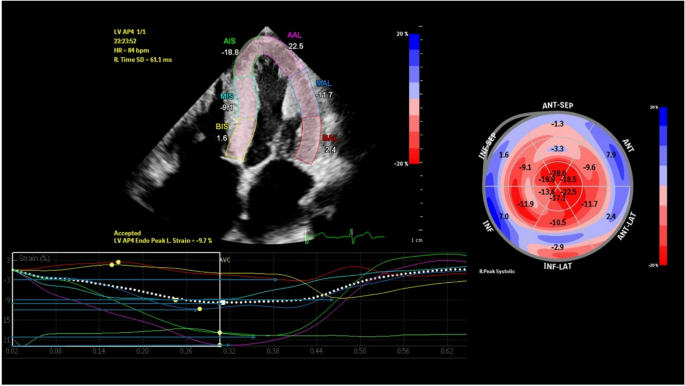

Echocardiographic assessment revealed that Groups 1A and 1B displayed greater LV wall thickness, LV mass index, left atrial area and volume, alongside reduced LV ejection fraction (LVEF), more advanced diastolic dysfunction, and an ‘apical sparing’ pattern, compared to the other groups (p < 0.001) (Table 2). Additionally, participants in Groups 1A and 1B exhibited significantly elevated right ventricle (RV) wall thickness, larger right atrial area and volume, reduced RV systolic function (TDI RV S’, tricuspid annular plane systolic excursion (TAPSE), and RV outflow tract velocity time integral (VTI)), compared to the other study groups (p < 0.05 for all). The echocardiographic evaluation of LV longitudinal strain parameters revealed significant differences across groups in multiple parameters. Specifically, compared to Groups 2 and 3, Group 1 A and 1B exhibited significantly reduced GLS, and segmental longitudinal strain across the apical 2-, 3-chamber views (p < 0.001 for all). Significant differences were also observed in basal, mid, and apical segments, with Group 1B consistently showing lower strain values in most segments. This heterogeneous pattern of reduced strain, with more pronounced impairment in certain regions compared to others, likely reflects the patchy distribution of amyloid infiltration within the myocardium in ATTR CA, resulting in ‘apical sparing’ pattern. Furthermore, Groups 1 A and 1B exhibited significantly greater mechanical dispersion compared to Groups 2 and 3 (Fig. 1).

Imaging results in a patient with hereditary transthyretin amyloidosis in apical 4-chamber view are consistent with advanced cardiac involvement and increased value of LV mechanical dispersion to 92 [ms], which was defined as the standard deviation of the time from QRS peak in electrocardiogram to peak longitudinal strain across the entire cardiac cycle. Horizontal blue arrows indicate contraction durations in each segment.